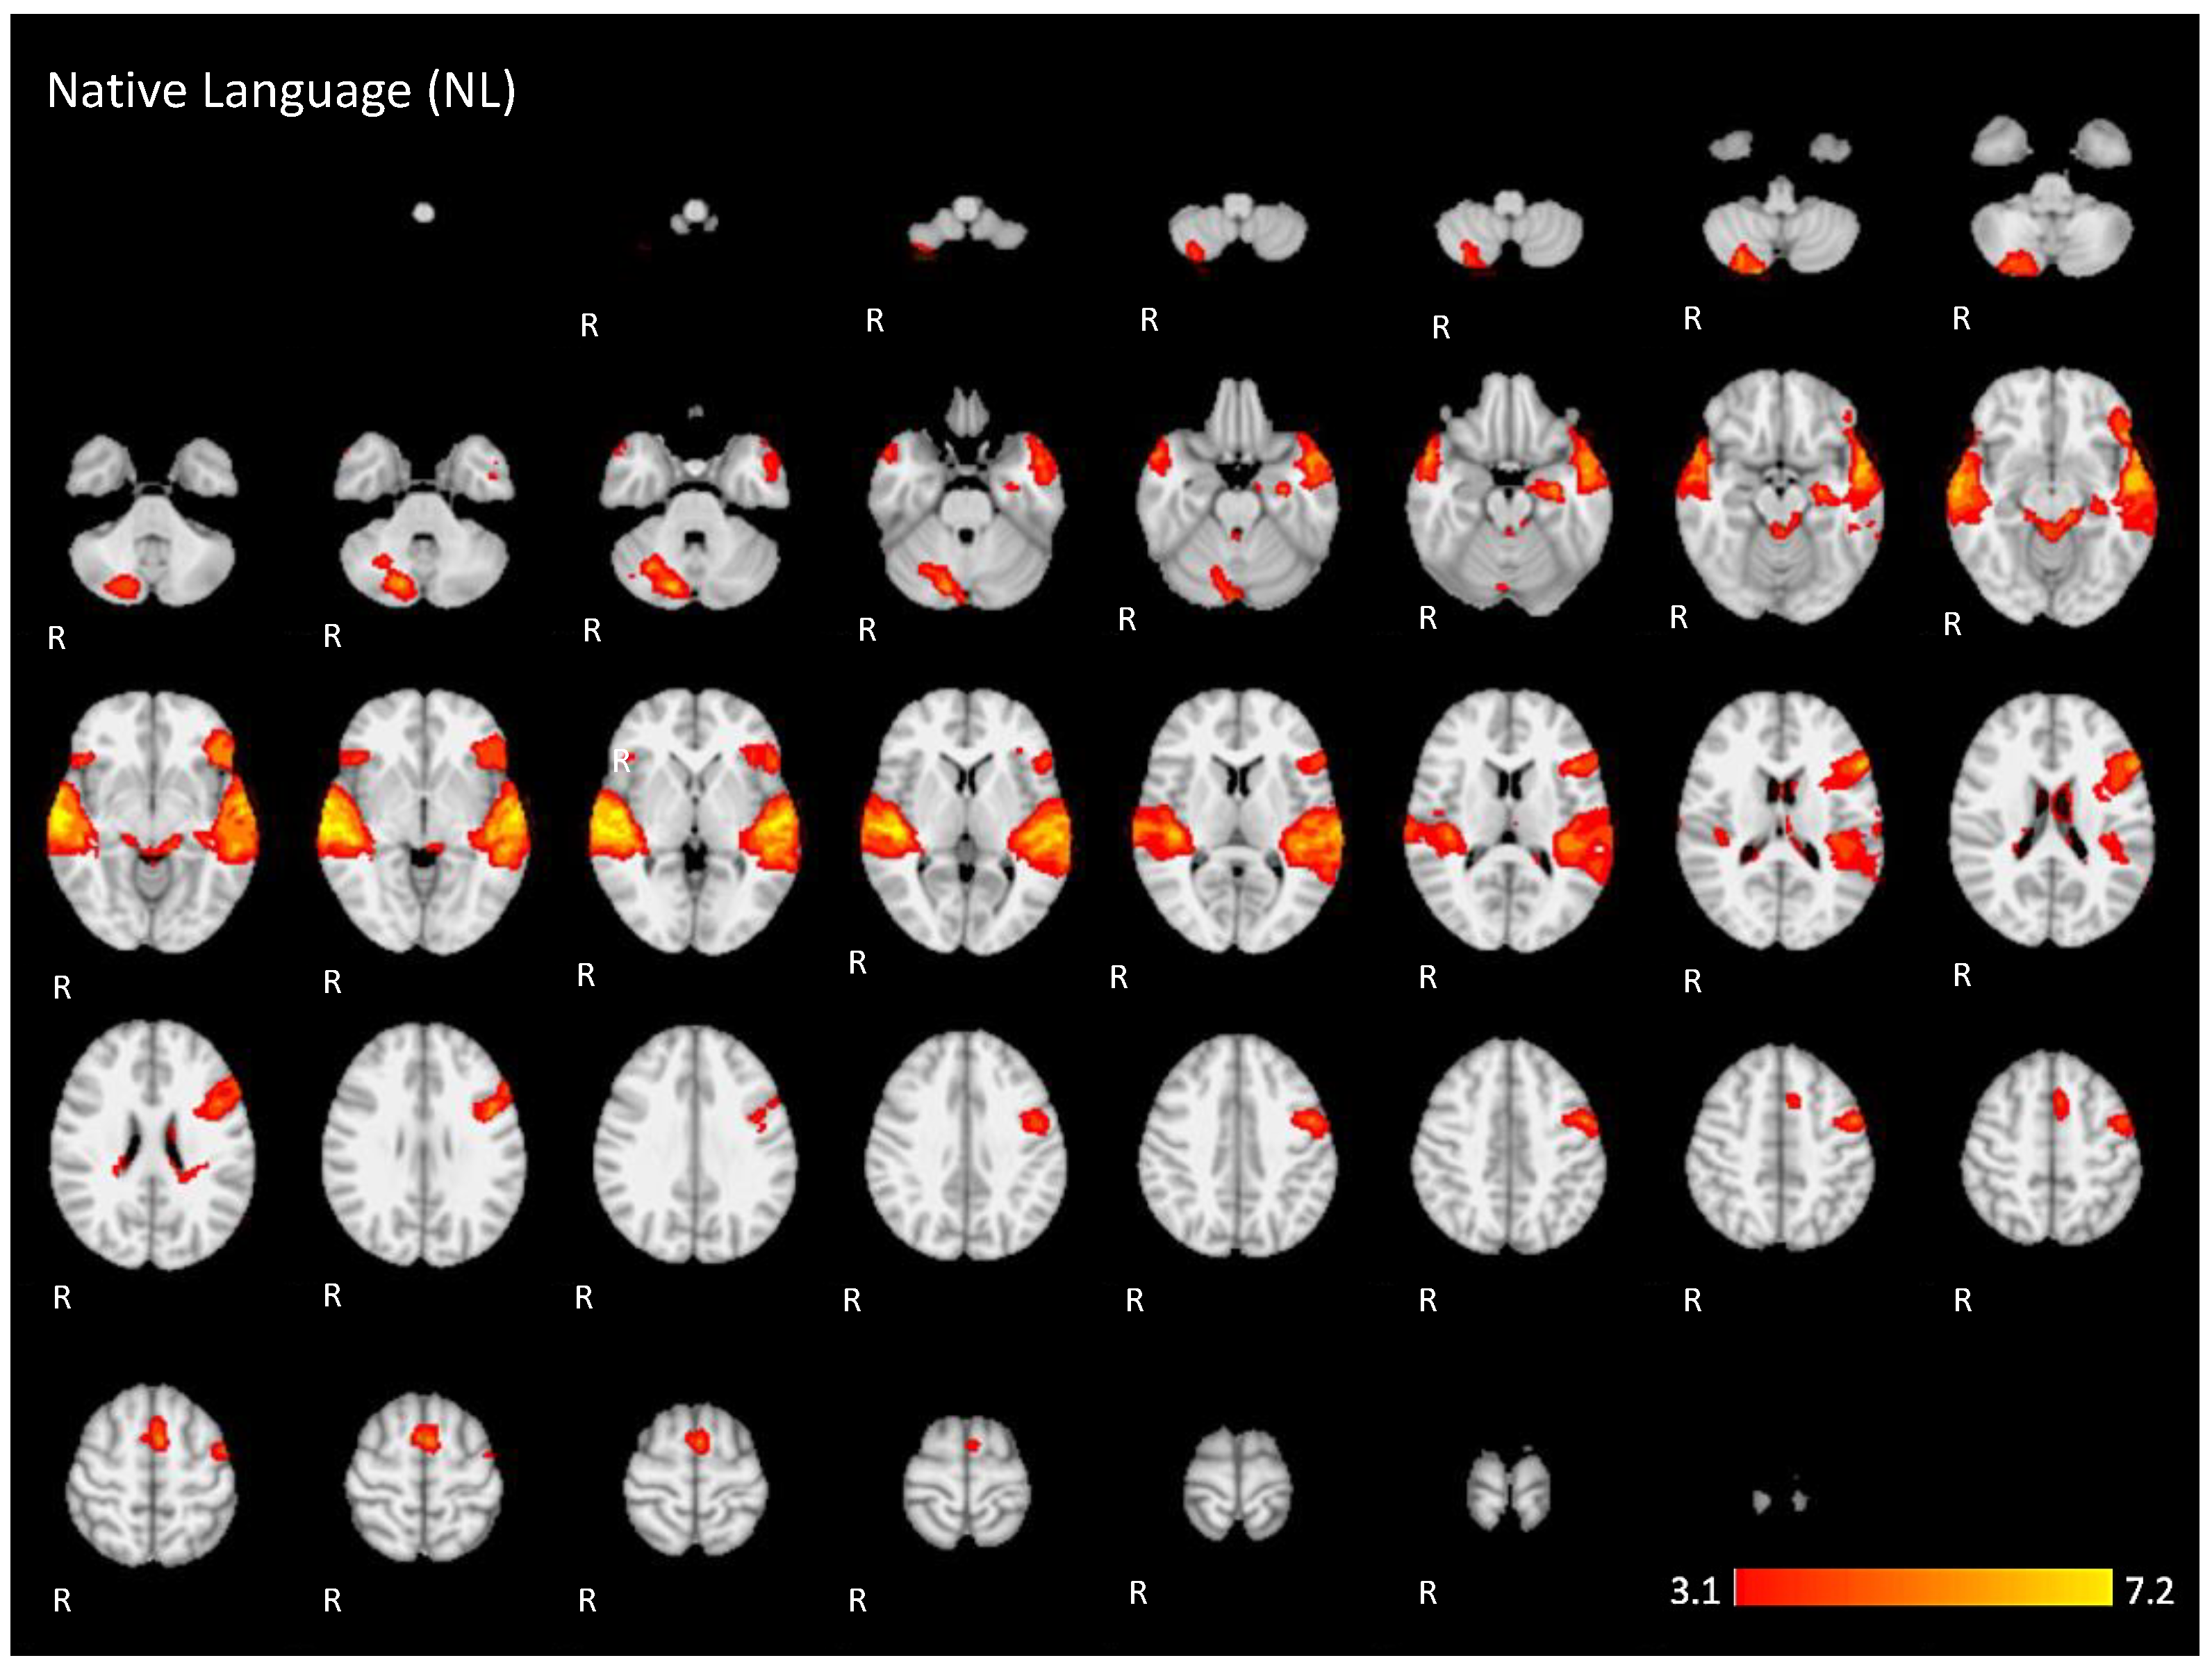

Appendix A. The 2D fMRI Maps of All Brain Slices for Both Active Conditions (NL, UL) and for Both Contrasts (NL > UL and UL > NL)

| NL | 7.14 | −58 | −16 | 0 | Left superior temporal gyrus |

| 7.24 | 62 | −14 | −8 | Right middle temporal gyrus | |

| 6.18 | 16 | −78 | −30 | Posterior lobe of right cerebellum | |

| 5.6 | −4 | 4 | 58 | Left supplementary motor cortex | |

| 5.25 | 0 | −40 | −14 | Anterior lobe of cerebellum | |